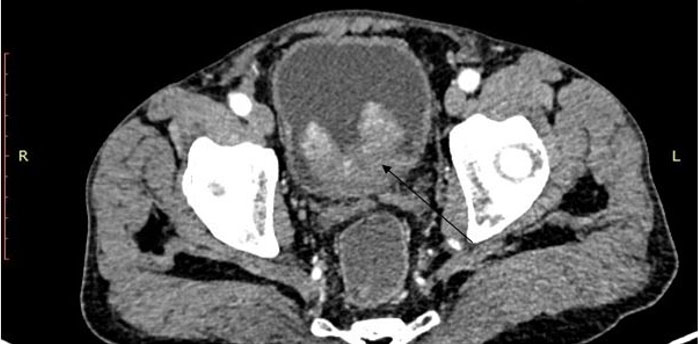

A particular form of inflammatory pseudotumor of the lung: The plasma cell granuloma

Keywords: Inflammatory pseudotumor, Lung, Plasma cell granuloma